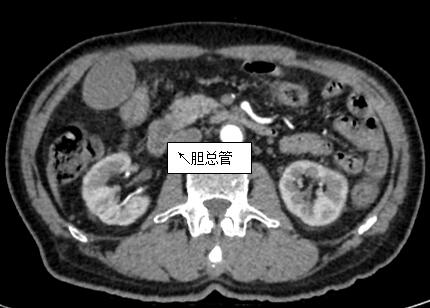

69歲王姓患者,因“發(fā)現(xiàn)無痛性黃疸1月”入院,根據(jù)患者病史,患者診斷傾向于壺腹部腫瘤所致梗阻性黃疸。予以完善腹部CT及上腹部MRI加MRCP均顯示肝內外膽管擴張,未發(fā)現(xiàn)明顯膽管,胰腺及十二指腸乳頭部腫瘤,且患者CA199正常。以前醫(yī)院未引進超聲內鏡,這類患者到此就遇到診斷瓶頸。此患者經過消化內科張丹霞副主任醫(yī)師完善超聲內鏡檢查后,可以清楚顯示膽總管下段壁內軟組織占位?;颊咄ㄟ^超聲內鏡檢查診斷明確,轉至肝膽外科行手術治療。

上腹部CT圖片

膽總管小腫瘤性病變CT及MRI檢查陽性率偏低,因其低代謝特征,PET-CT陽性率也偏低,超聲內鏡對這類疾病的診斷陽性率是所有檢查中最高的,且可行穿刺活檢進一步確診病灶性質。